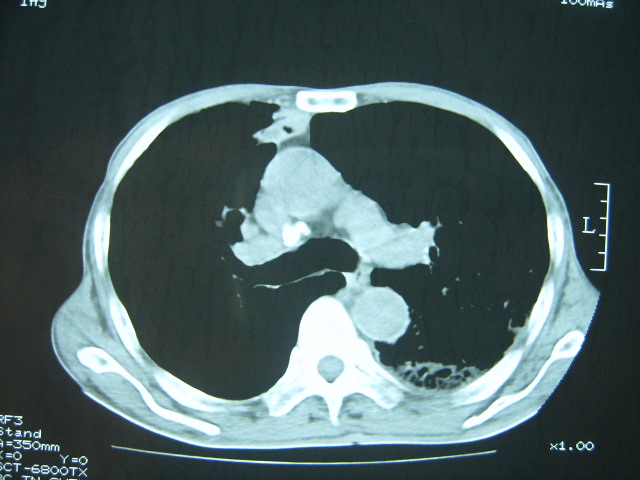

男74岁,咳嗽,寒战,低烧。有糖尿病史。

糖尿病并发肺脓肿建议治疗后复查

考虑:糖尿病合并:1、左下肺炎继发肺脓肿;

2、双肺结核。

考虑1、双肺结核2、左下肺脓肿